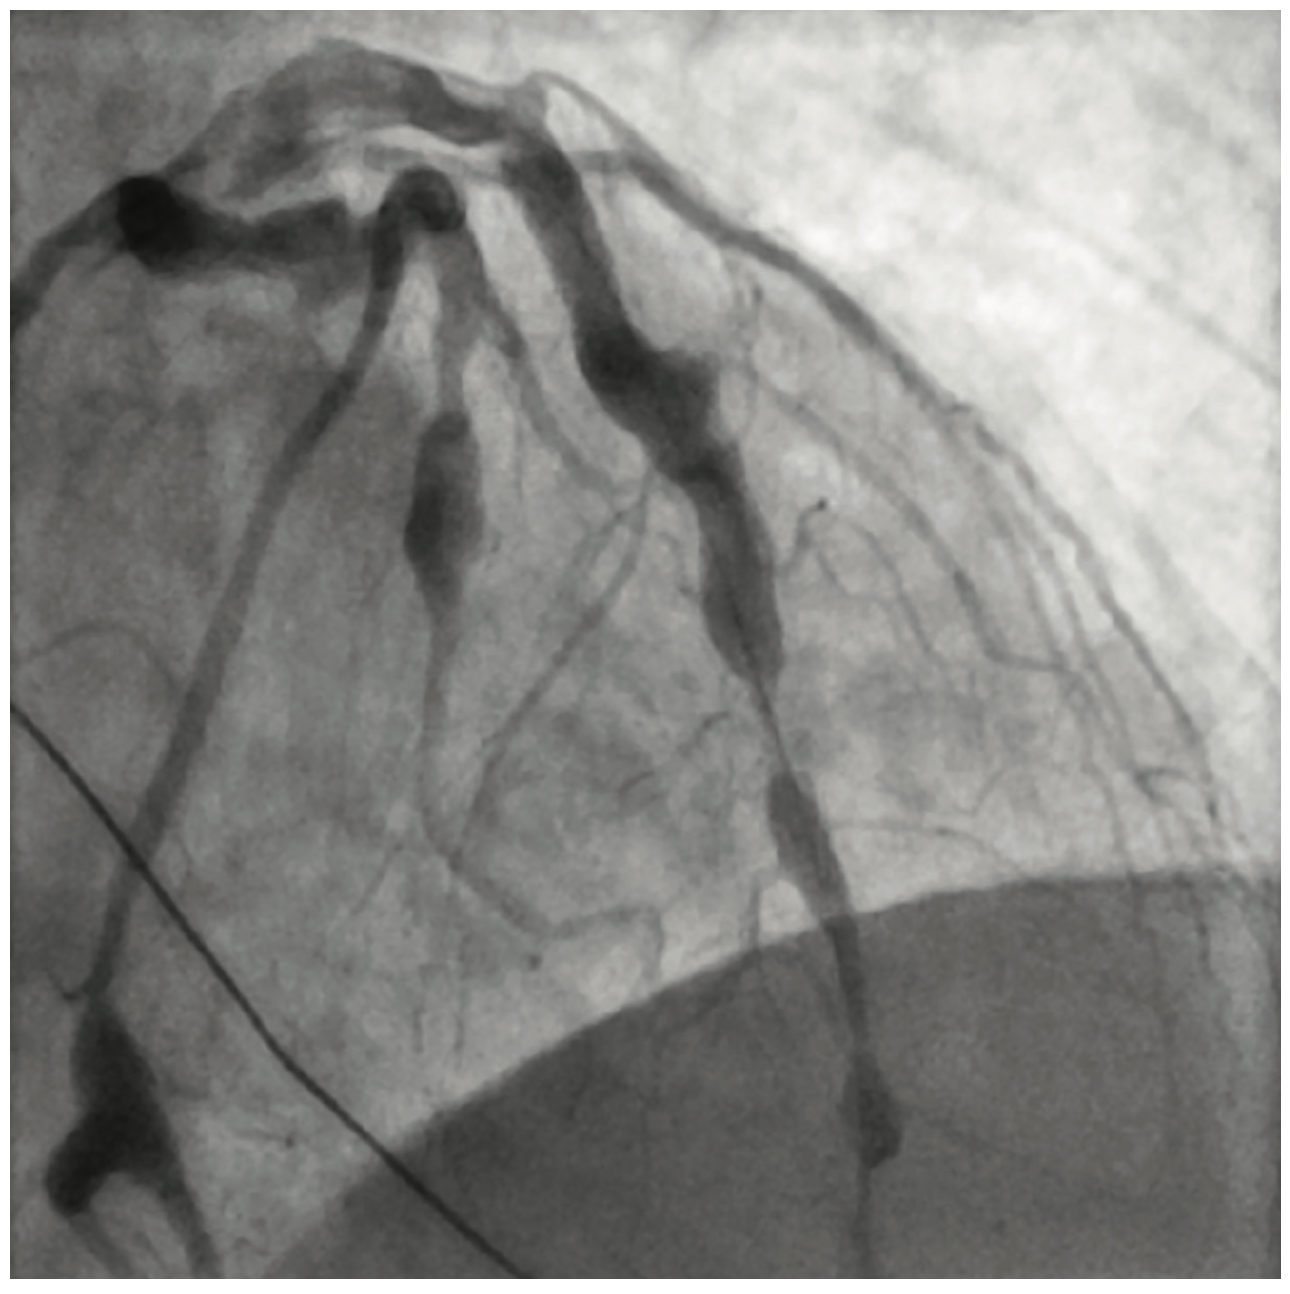

Figure 4. Stent placement in proximal LAD.

Cardiac catheterization showed total occlusion of the left anterior descending artery (LAD) with multiple coronary aneurysms in the LAD, left circumflex (LCx), and right coronary arteries. There was TIMI 0-1 slow flow within the coronary aneurysms. An eptifibatide bolus and drip was started. Aspiration thrombectomy using an Export catheter (Medtronic) and then rheolytic thrombectomy using an AngioJet catheter was performed on the proximal and mid LAD. A 4.0 x 16 mm bare metal stent was placed. However, the patient became hypotensive in the cath lab and a balloon pump was inserted. Prior to leaving the lab, there was resolution of the ST segment elevations. The patient was started on both a heparin drip and low-dose dopamine drip.